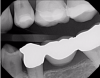

Figure 4 through Figure 11 compare various imaging modalities in three different cases, illustrating the potential of these devices to improve diagnostic capabilities.

Fig 7. Case 2. Bitewing radiograph shows no indication of interproximal or recurrent caries around the composite restoration on tooth No. 13.

Figure 7

Fig 8. Case 2. NIR transillumination image shows darkness around the composite and in the cracked region, indicating caries in both areas.

Figure 8